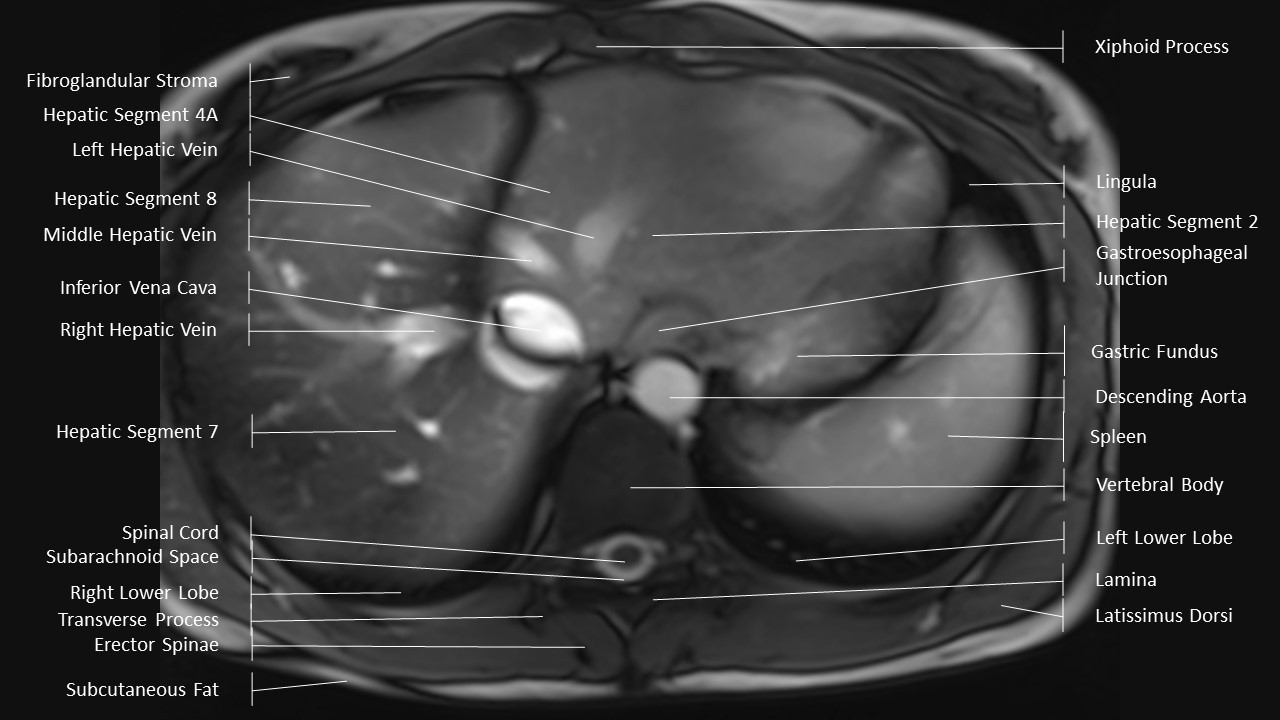

Axial Series